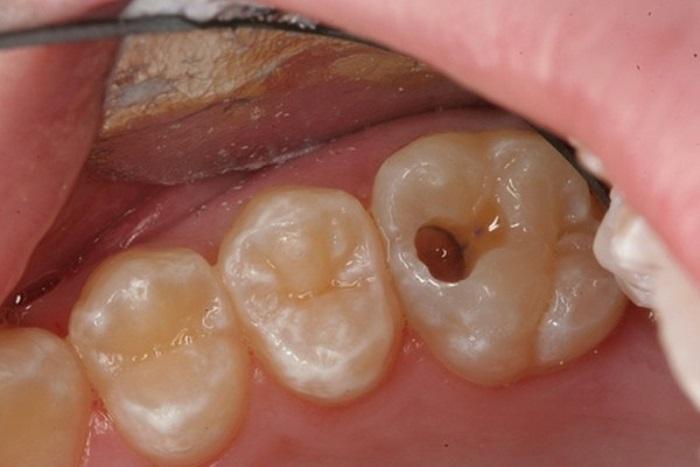

Gọi điệnNha khoa Bệnh viện JW Hàn Quốc là địa chỉ tiên phong trong việc chữa trị các bệnh lý răng miệng an toàn, đặc biệt là chữa tuỷ răng. Tủy răng tổn thương thưởng biểu hiện với triệu chưng đau, sưng hoặc tê buốt… khi tiếp xúc với đồ ăn nóng, lạnh. Trường hợp bệnh trở nặng được coi là chết tủy, việc giữ lại những mô tủy đã chết sẽ khiến tình trạng viêm nhiễm ngày càng nặng nề hơn, dẫn đến áp xe quanh chân răng, nhiễm trùng máu…ảnh hưởng đến sức khỏe và chất lượng cuộc sống. Chính vì vậy, lấy tủy răng là việc làm rất cần thiết. Quá trình điều trị tủy răng thực chất là việc loại bỏ những mô tủy đã bị nhiễm trùng, hoại tử và làm sạch ống tủy. Sau đó trám bít ống tủy lại bằng chất trám nhân tạo, ngăn chặn sự xâm nhập của vi khuẩn và mảng bám.

Gọi điệnCần biết rằng viêm tủy răng là một bệnh lý phổ biến, gây ra nhiều đau nhức khó chịu cho người bệnh. Các nguyên nhân dẫn đến viêm tủy là: sâu răng, viêm nha chu, chấn thương răng, thường xuyên ăn uống thực phẩm quá nóng hoặc quá lạnh. Chữa tủy - Nội nha là công đoạn điều trị được áp dụng cho những trường hợp răng sâu quá lớn, lộ tủy và buộc phải lấy tủy để tránh gặp tình trạng đau nhức dữ dội. Bằng cách lấy sạch vi khuẩn và phần tủy bị viêm trong ống tủy, sau đó trám bít chặt hệ thống ống tủy nhằm ngăn chặn vi khuẩn xâm nhập, nhờ đó loại bỏ viêm nhiễm và bảo tồn mô răng còn lại.